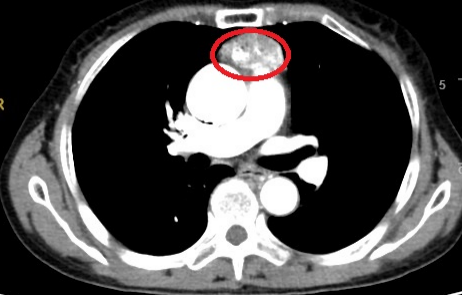

消化病中心立即邀请胸心外科副主任、副主任医师蒋浩进行会诊。经过仔细询问病史、查体,并结合胸部CT等影像检查,蒋浩主任认为:孙阿姨为前纵隔占位,大小约5.3×2.8cm,有手术指征,建议进行手术治疗。

▲CT影像显示:患者前纵隔占位